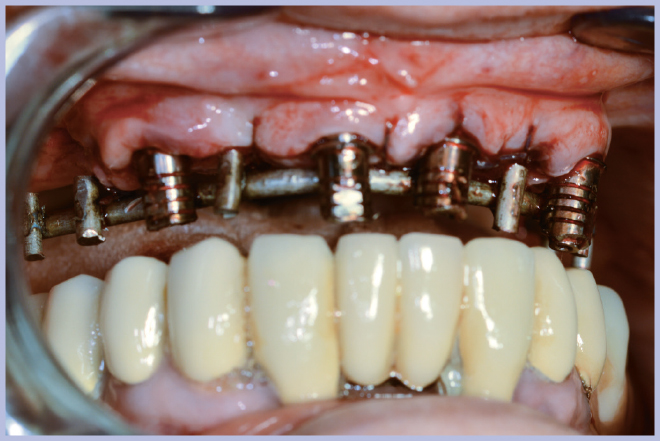

Sui monconi, dopo aver attivato la connessione a cono Morse (Fig. 3), sono state fissate le apposite cappette in titanio con le viti a testa alta (Fig. 4) ed è stata realizzata un’armatura di rinforzo per mezzo di una sincristallizzatrice intra-orale. In particolare la barra è stata ottenuta mediante saldatura sulle cappette di un filo pre-modellato di titanio grado 2 (Figg. 5, 6).

- Figg. 5, 6 – Struttura di rinforzo ottenuta saldando intra-oralmente un filo di titanio alle cappette

- Fig. 6